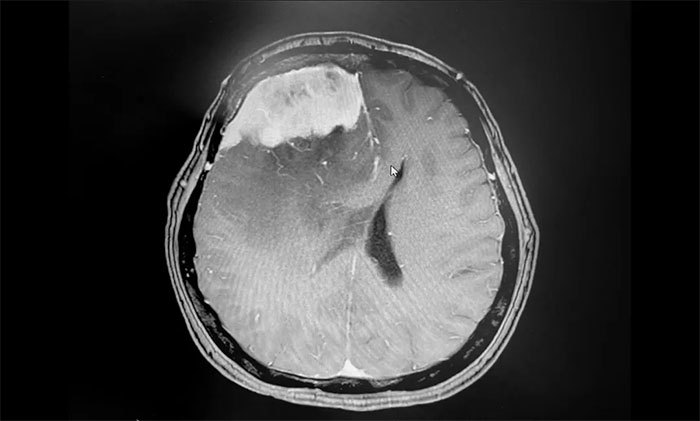

入院后,于耀宇主任为章女士完善检查。头颅MRI增强示:右侧额叶不规则团块状异常信号影,边界不清,最大直径约5.6cm,大小与鸭蛋相仿。病灶周边有大片水肿信号影;邻近大脑脚、胼胝体及双侧侧脑室受压、变形;中线结构左偏。

▲ 肿瘤大小与鸭蛋相仿

▲ 术后影像,肿瘤已切除